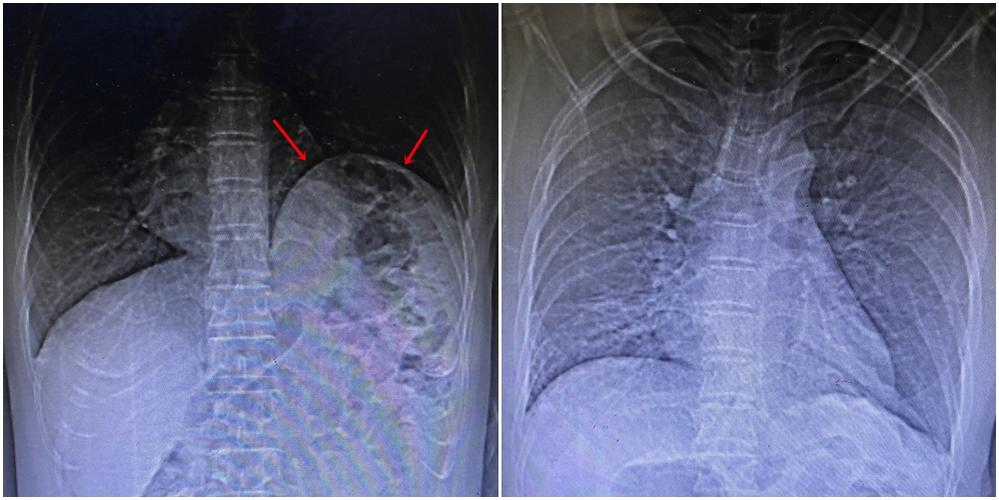

Kết quả chụp X-quang và cắt lớp vi tính cho thấy, bệnh nhân có vòm hoành trái cao khiến các tạng di chuyển lên trên gây xẹp thụ động nhu mô phổi lân cận. Các bác sĩ chẩn đoán bệnh nhân bị nhão cơ hoành trái và chỉ định phẫu thuật nội soi tạo hình cơ hoành.

Hình ảnh x-quang của bệnh nhân bị nhão cơ hoành trái khiến tạng dưới ổ bụng di chuyển lên trên, trước và sau phẫu thuật. Ảnh BVCC